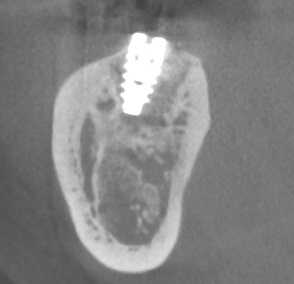

本日はラテラルスリットというサイナスリフトの侵襲を少なくした 我々で考えたオペでした。 サイナスリフトなどのやや難しいといわれるオペは 骨材料の改良や骨と優位に接着するインプラント体の改良 オペ法の改良により 腫れにくく 埋入したいところにインプラントを なるべく短期間に成功させるこ…